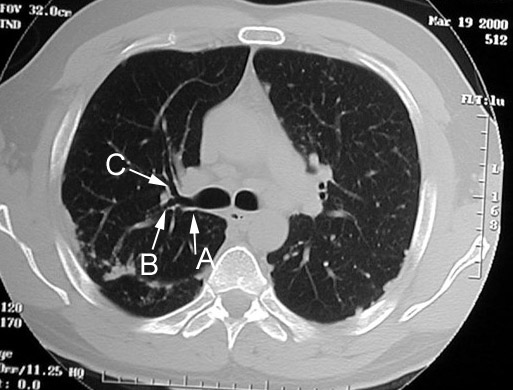

Q: You are looking at section at the level of RUL bronchus (at or just below carina). Identify the labeled airways.

Answer

They appear tubular in this section, since all of them course horizontally

Origin of apical segment of upper lobe superimposed on the distal portion of RUL as rounded decreased density not evident in this section.